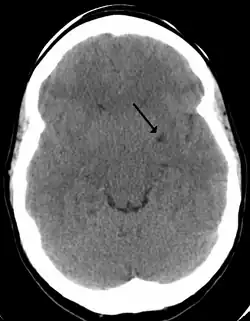

Dilated perivascular spaces are categorized into three types:[7]

- Type 1 are located on the lenticulostriate arteries projecting into the basal ganglia

- Type 2 are located in the cortex following the path of the medullary arteries

- Type 3 are located in the midbrain

Perivascular spaces are most commonly located in the basal ganglia and white matter of the cerebrum, and along the optic tract.[13] The ideal method used to visualize perivascular spaces is T2-weighted MRI. The MR images of other neurological disorders can be similar to those of the dilated spaces. These disorders are:[7]

Perivascular spaces are distinguished on an MRI by several key features. The spaces appear as distinct round or oval entities with a signal intensity visually equivalent to that of cerebrospinal fluid in the subarachnoid space.[7][14][15] In addition, a perivascular space has no mass effect and is located along the blood vessel around which it forms.[14]

The clinical significance of perivascular spaces comes primarily from their tendency to dilate. The importance of dilation is hypothesized to be based on changes in shape rather than size.[13] Enlarged spaces have been observed most commonly in the basal ganglia, specifically on the lenticulostriate arteries. They have also been observed along the paramedial mesencephalothalamic artery and the substantia nigra in the mesencephalon, the brain region below the insula, the dentate nucleus in the cerebellum, and the corpus callosum, as well as the brain region directly above it, the cingulate gyrus.[5] Upon the clinical application of MRI, it was shown in several studies that perivascular space dilation and lacunar strokes are the most commonly observed histological correlates of signaling abnormalities.[13]